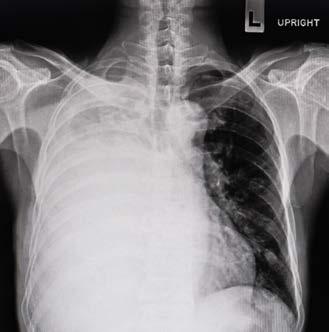

Lung Cancer

‘It’s Simple: Catch it Early’

Harvey Edelman’s outcome exemplifies Mount Sinai’s pioneering approach to successfully treating lung cancer, which focuses on early detection and minimally invasive surgical treatment, and is making great strides in curing a particularly deadly cancer and preserving quality of life for patients.

“He did beautifully,” says Raja Flores, MD, Chairman of the Department of Thoracic Surgery and the Steven and Ann Ames Professor in Thoracic Surgery, who performed the video-assisted thoracoscopic surgery (VATS) lobectomy, which removes the small tumor through three tiny incisions. “He’s cured and immersed back into his productive life.”

Lung cancer is the leading cause of all cancer deaths in the U.S. and worldwide, and is too often caught once the tumor is too large to successfully resect. A surgery such as VATS lobectomy, which Dr. Flores has made the gold standard in lung cancer surgery, is possible only when the tumor is found at stage one, measuring about 1 to 2 centimeters.

“Lung cancer becomes a curable disease when it is found early and treated,” says Claudia Henschke, PhD, MD, Director of the Lung and Cardiac Action Program and Professor of Radiology.

Dr. Henschke and David Yankelevitz, MD, Professor of Radiology and Director of the Lung Biopsy Service, are renowned for changing the equation in lung cancer diagnosis. They were the founding investigators of the Early Lung Cancer Action Program (ELCAP), the first study to demonstrate that low-dose computed tomography (CT) scans can reliably diagnose early stage lung cancer in people at high risk for the disease. Before ELCAP, the prevailing methods of screening, such as chest X-rays, could seldom detect stage one

tumors, which are the earliest and most treatable manifestations of lung cancer.

Their groundbreaking work on screening has led to major advances in diagnostic guidelines and nationally and internationally. Among other findings, International (I)-ELCAP (the expanded version of ELCAP, with about 80,000 participants in 10 countries) found that annual CT screening led to more than 80 percent of lung cancers being diagnosed at the earliest stage, stage one, and that the curability of these CT-detected stage one tumors was between 80 to 90 percent, a vast improvement from just five – 10 percent curability today.